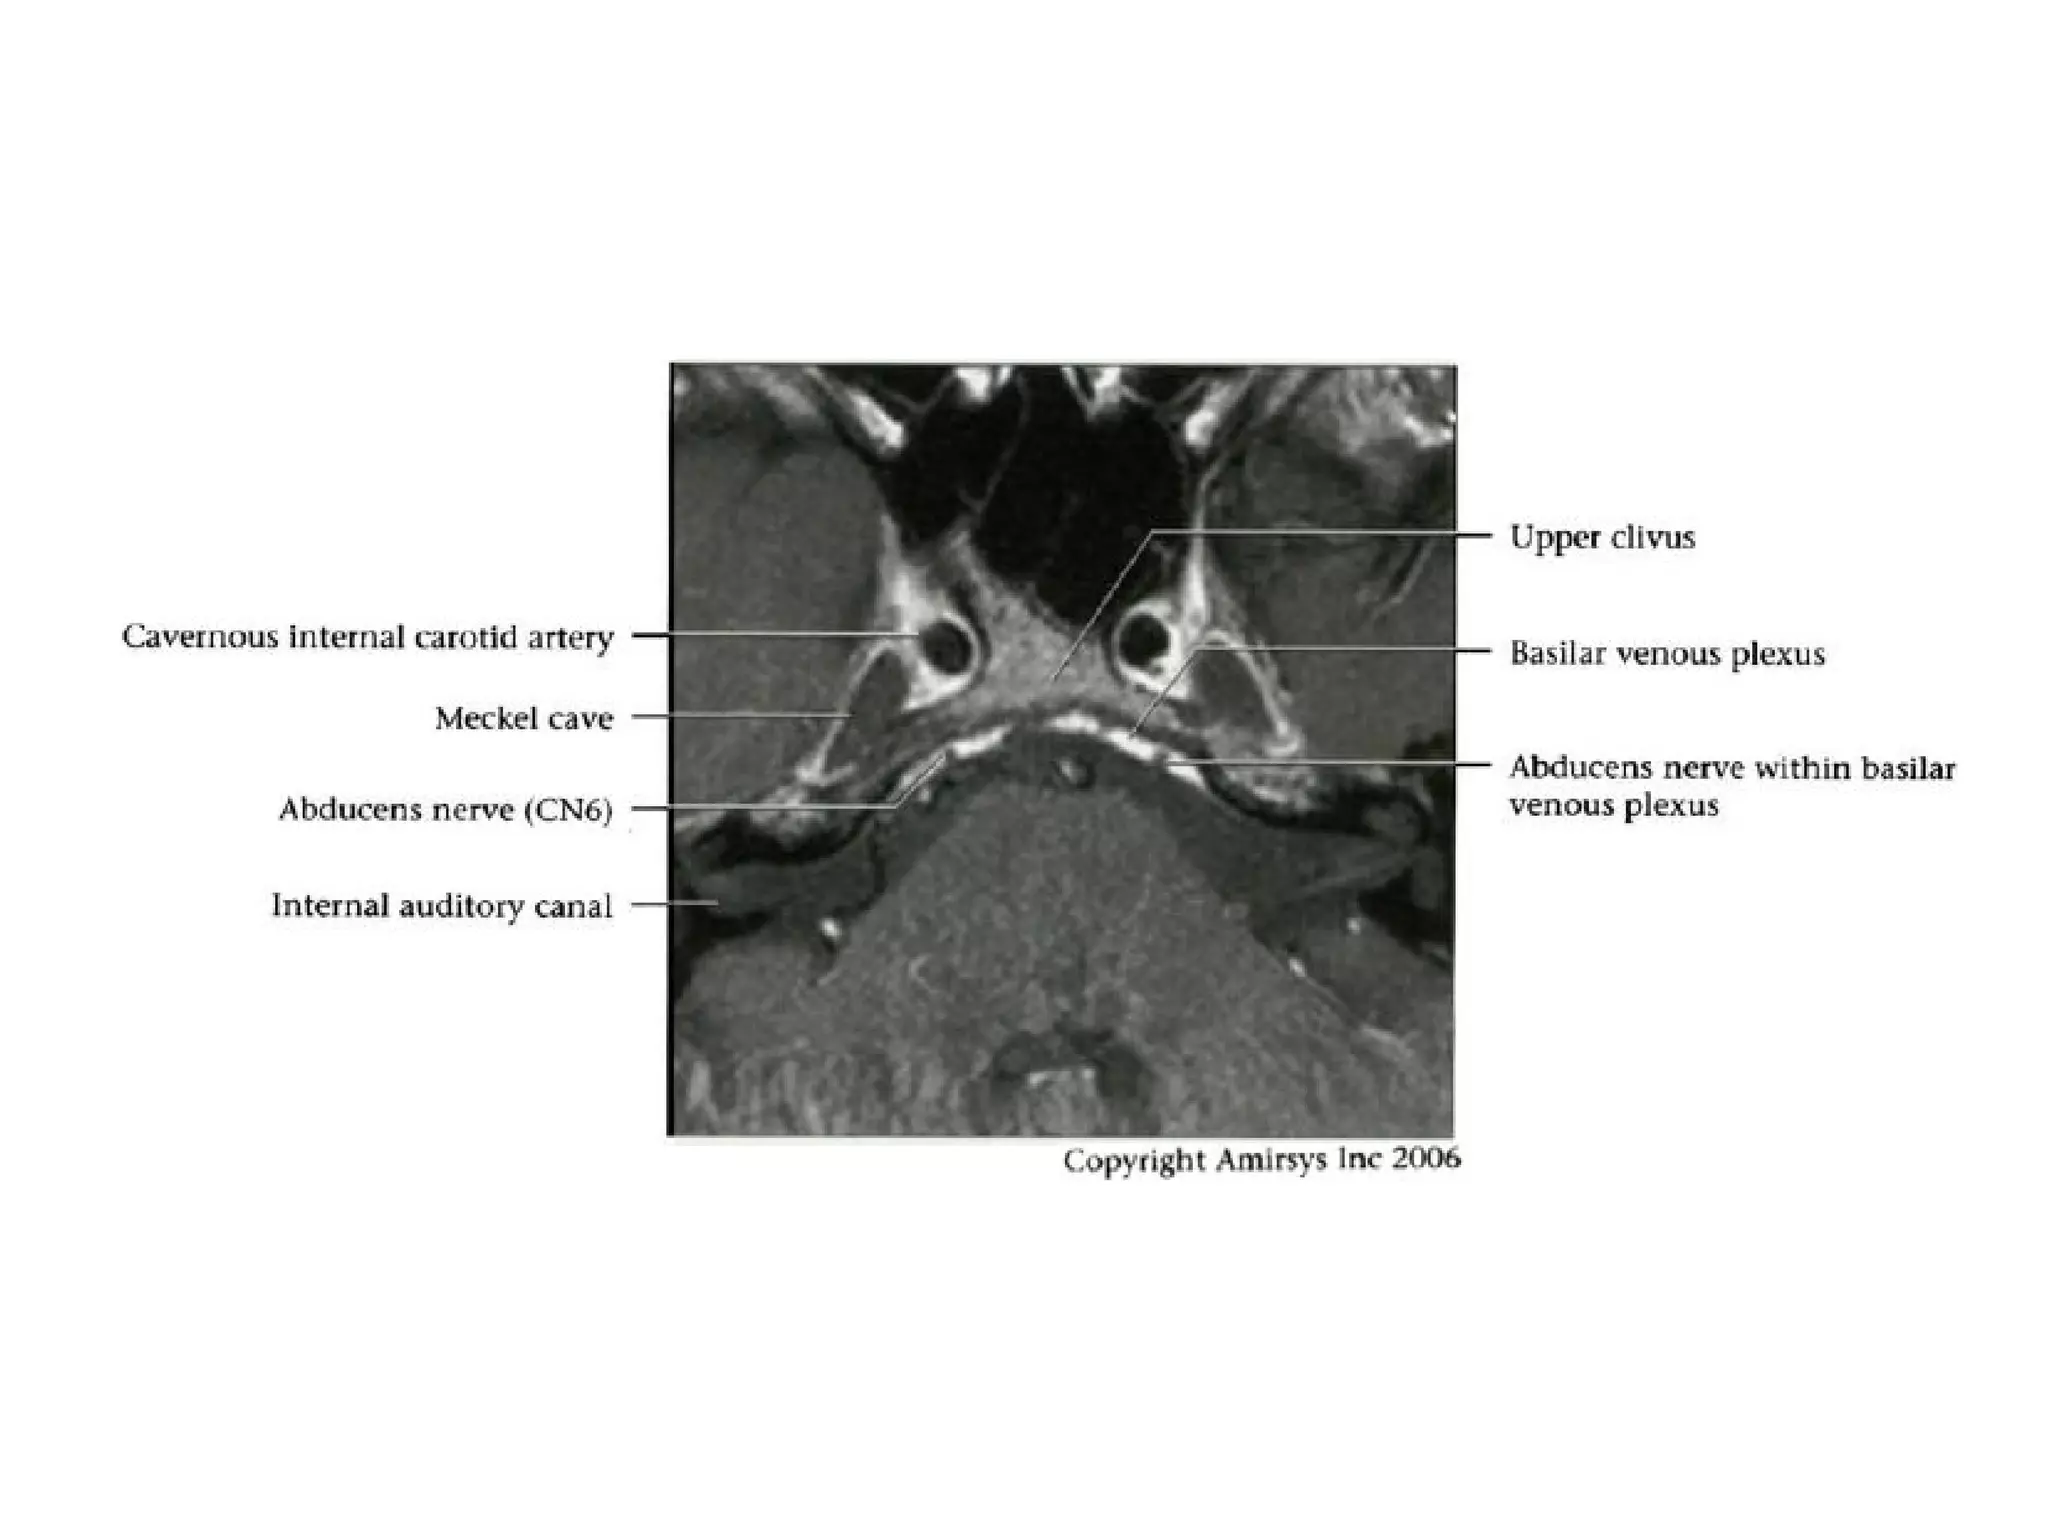

Cranial Nerve VI:

The Abducens Nerve

• The abducens nerve emerges from nuclei anterior to the

fourth ventricle, then courses anteriorly through the pons

to the pontomedullary junction and into the prepontine

cistern.

• After crossing the prepontine cistern in a posterior-to-

anterior direction, the abducens nerve runs vertically

along the posterior aspect of the clivus, within a fibrous

sheath called the Dorello canal.

• The nerve then continues over the medial petrous apex

and through the medial cavernous sinus, entering the

orbit through the superior orbital fissure to innervate the

lateral rectus muscle.

• It is important to note that the abducens nerve

runs almost the entire length of the clivus.

• Radiologists should be vigilant for clivus and

petrous apex abnormalities in the setting of

abducens nerve palsy.

• Although the abducens nerve lies near the

anterior inferior cerebellar artery and has a

similar caliber, the two structures course in

orthogonal directions and are thus easily

distinguished.

Abducens nerve.

Axial 0.8-mm-thick SSFP MR image at the level of the

pontomedullary junction shows both abducens nerves (arrows)

where they traverse the prepontine cistern.

The bottom of the pons (p) and the top of the medulla (m) are

visible in this section, and the cerebellopontine angle (CPA) and

basilar artery (arrowhead) are important anatomic landmarks.

Axial 0.8-mm-thick SSFP MR image shows the abducens nerve

where it enters the Dorello canal (arrow) along the posterior

aspect of the clivus.

Vascular landmarks include the basilar artery (black arrowhead)

and the anterior inferior cerebellar artery (white arrowhead).